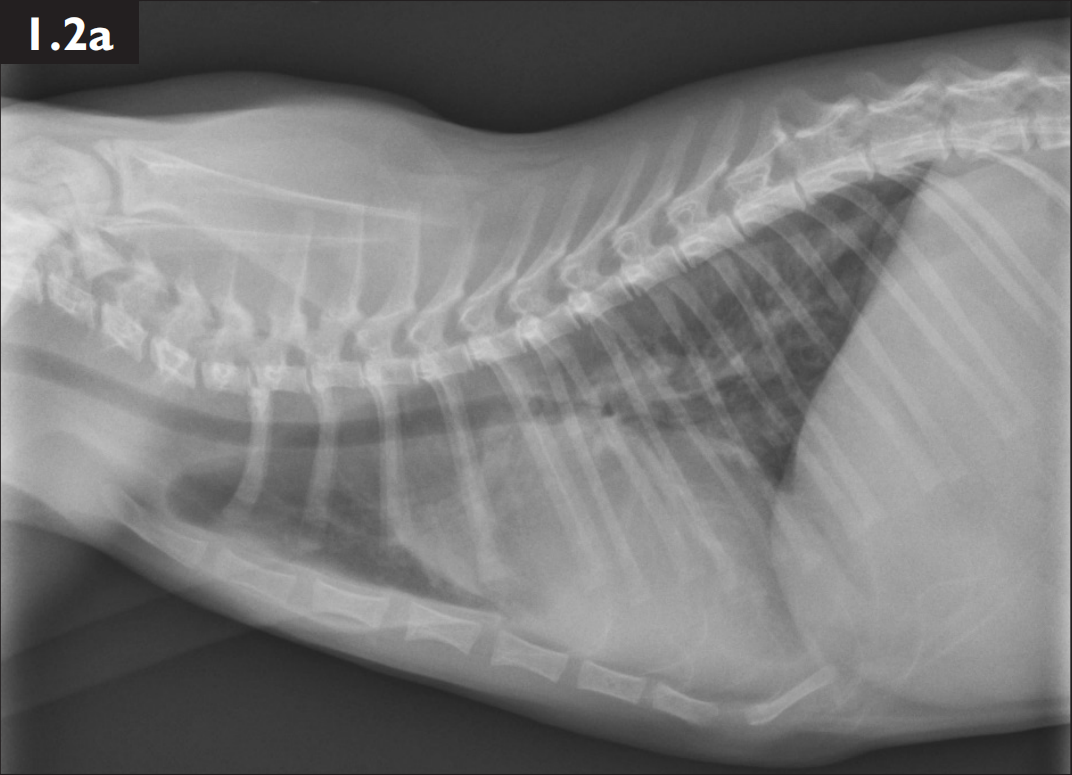

2犬猫胸腔积液和肺水肿的X光片诊断阅读 (1940)